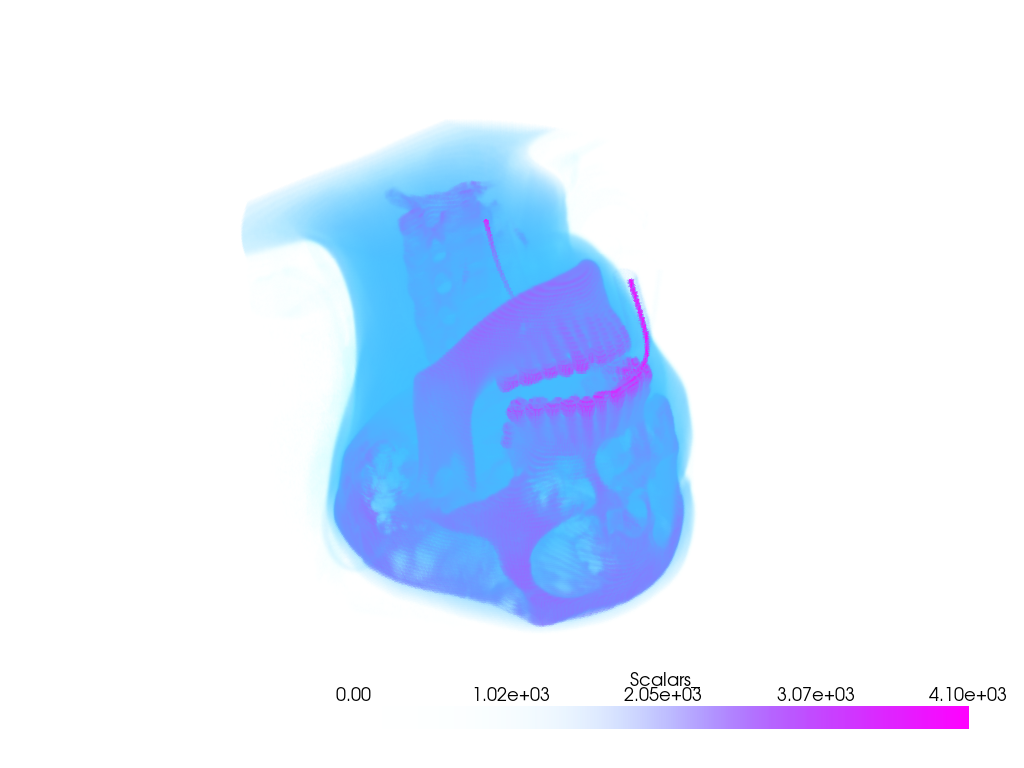

Download head dataset.

>>> import pyvista >>> from pyvista import examples >>> dataset = examples.download_head_2() >>> pl = pyvista.Plotter() >>> _ = pl.add_volume(dataset, cmap="cool", opacity="sigmoid_6") >>> pl.show()